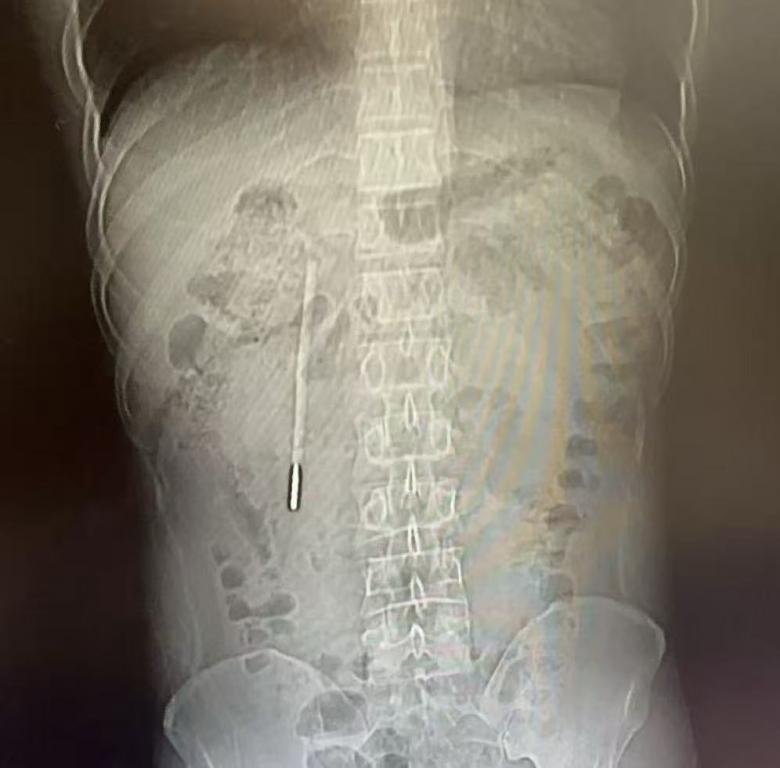

12岁时误吞的一根体温计,竟在肚子里“潜伏”了整整20年。近日,温州医科大学附属第一医院医护团队用内镜从患者王先生的十二指肠处取出体温计。

32岁的王先生最近腹部消化不好,前往温医大附一院龙港院区就诊。该院区医生对其做腹部CT检查,发现其十二指肠处有异物,高度怀疑是水银体温计,前端已抵在肠壁上,随时可能引发穿孔、大出血等严重后果。追问病史后得知,这根体温计是王先生12岁时不慎误吞的,当时因害怕不敢告知家长,其家长忙于工作疏于看管,而王先生的身体也没出现异样,也就没把此事放在心上。

该院内镜中心医护团队立即开展内镜下取物操作。由于体温计滞留时间长、位置深,且毗邻胆管胰管,操作空间狭窄,稍有不慎便会损伤肠壁。团队在相应器械的辅助下精准定位,用圈套器套住体温计一端,缓慢轻柔提拉,仅用20分钟便成功将其完整取出,取出的体温计除刻度消失外,外观完好无损。